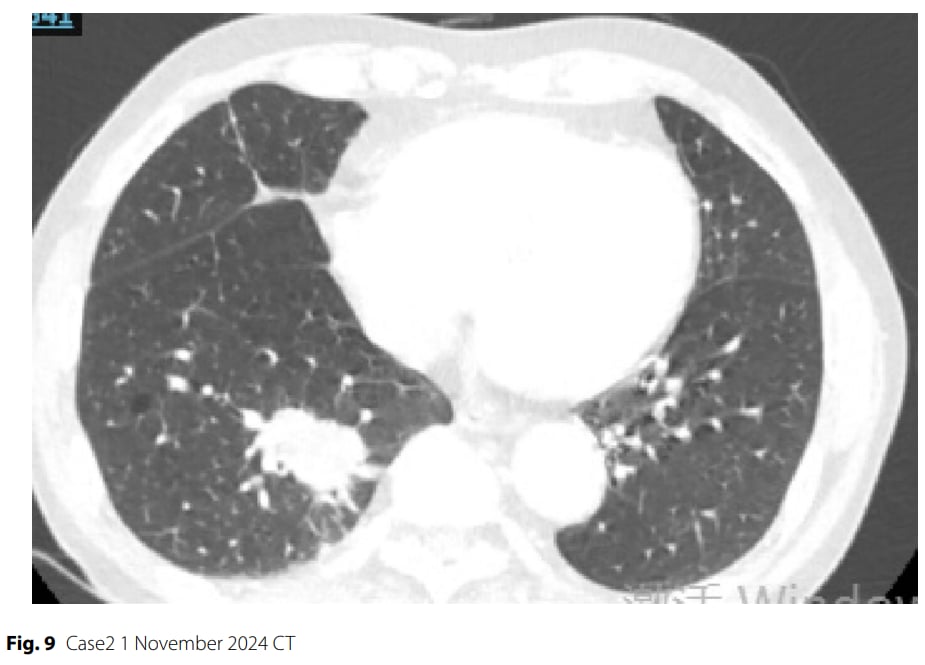

▲图9 病例2 2024年11月1日CT

治疗过程:患者接受了3个周期的“依托泊苷+卡铂+斯鲁利单抗”新辅助治疗。初期影像学显示肿瘤部分缓解(缩小68.3%),但第三个周期治疗后却出现反常进展(肿瘤增大)。影像学评估为疾病稳定(SD),具备手术切除条件。患者强烈要求手术,经多学科团队会诊,最终决定进行手术。随后患者接受了电视胸腔镜下肺叶切除术。

- 疾病进展(PD):术后病理证实仍有残留的低分化癌细胞,伴血管侵犯。

- 分子标志物恶化:术后分子检测显示,虽然MET、PTEN、MYC的变异丰度或拷贝数有所下降,但TP53基因突变丰度保持稳定。更重要的是,肿瘤突变负荷(TMB)从治疗前的23.72个突变/兆碱基不降反升至28.13个突变/兆碱基。治疗后PD-L1表达水平也升高(TPS=20%,CPS=30%)。

失败原因分析:病例2的治疗结局令人警醒。尽管基线TMB较高,且PD-L1表达在治疗后升高,但肿瘤却表现出治疗进展。这可能说明肿瘤内部存在更复杂的耐药机制或免疫逃逸策略。MYC基因扩增、TP53功能获得性突变以及MET基因融合等持续存在的致癌驱动基因改变,可能共同促进了肿瘤的进展。TMB不降反升,PD-L1表达升高,这些反常的分子变化可能预示着肿瘤的异质性增加,以及免疫微环境对治疗的抵抗。